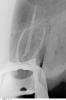

x3m Опубликовано 30 марта, 2010 Поделиться Опубликовано 30 марта, 2010 В некоторых ситуациях керамические вкладки являются хорошей альтернативой коронкам. Надо смотреть на количество оставшихся тканей зуба.конечно, кламп мешает увидеть все, и принимать решение нужно после осмотра.имхо, это не тот случай, где можно вкладкой. Ссылка на комментарий